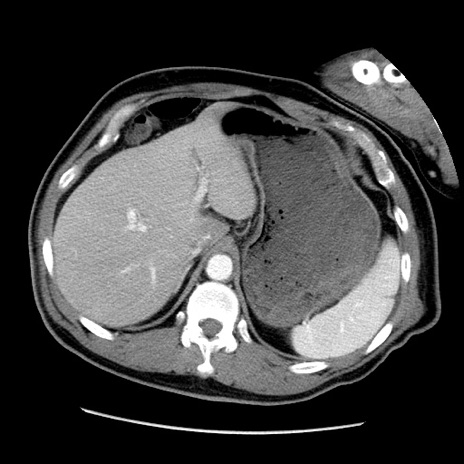

症例22(横断像)

【症例】50歳代男性

【主訴】腹痛

【現病歴】AVMからの被殻出血のため回復期リハ病棟入院中。 本日午後3時頃急に下腹部痛が出現した。

【既往歴】AVM、被殻出血、虫垂炎、高血圧

【身体所見】意識晴明、左半身不全麻痺、会話の理解は良好、36.5°C、腹部:膨隆、全体に板状硬、下腹部正中に圧痛点あり、反跳痛-、筋性防御不明、右下腹部にope scar

【データ】WBC 9400、CRP 0.06